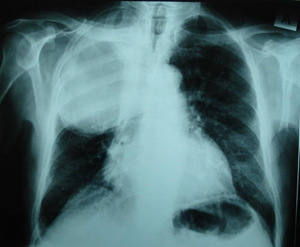

Εικόνα 1

Οπισθιο-προσθία ακτινογραφία θώρακος. Διακρίνεται ευμεγέθης ομοιογενής σκίαση στο δεξιό ημιθωράκιο στο άνω και μέσο πνευμονικό πεδίο.